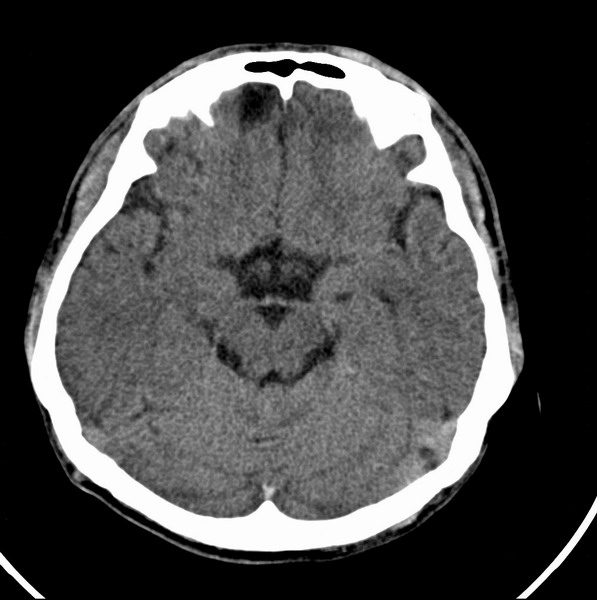

标题: CT21509:额叶低密度影

男、29

突发痴呆,失语,记忆减退,反应迟钝二十小时。

右侧额叶低密度影,边界清晰,无占位效应,符合:额叶皮质脑软化灶。

双额叶脑沟增深增宽,皮质性脑萎缩可以考虑么?

左额叶也有类圆形低密度影,同右侧低密度灶近颅底一层同层,病灶周脑实质密度似稍高,成环状,这个没有问题么?

考虑右侧额叶脑软化灶;建议必要时行mri检查排除其他。

考虑皮质软化灶。不考虑胶质瘤,是因为胶质瘤一般发生于白质内。